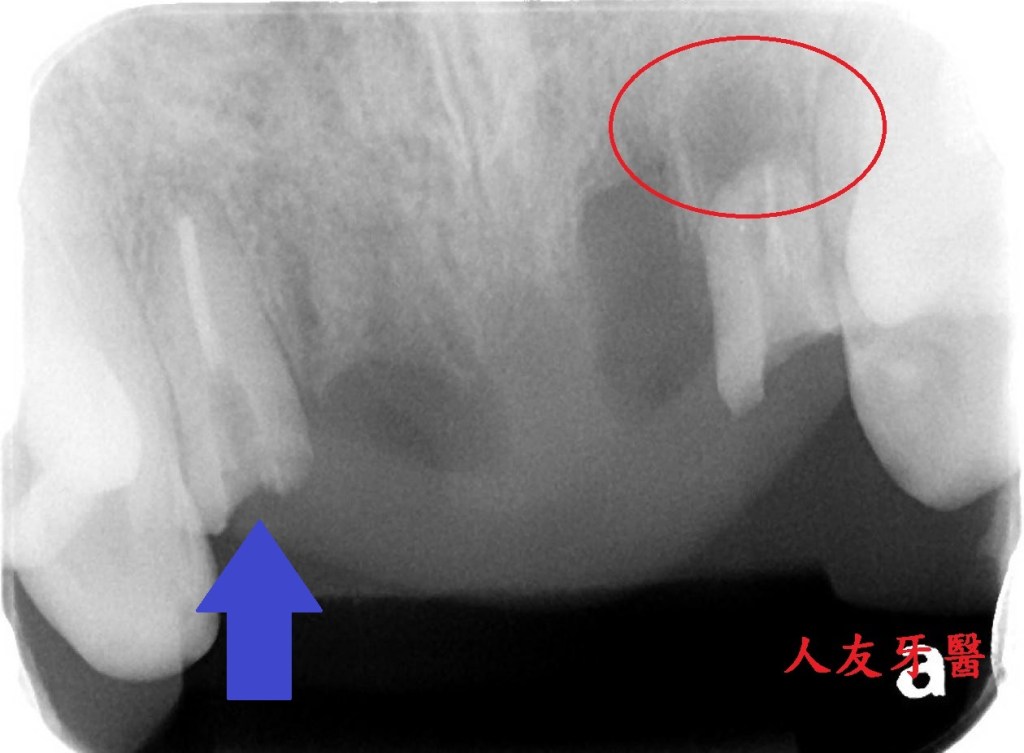

想詢問周醫師如何處理。醫師看了X-RAY發現右邊側門牙紅色圓圈的地方有病變,有可能留不住。左邊側門牙藍色箭頭牙齒有裂到肉,也可能留不住。經過討論後建議都拔除。